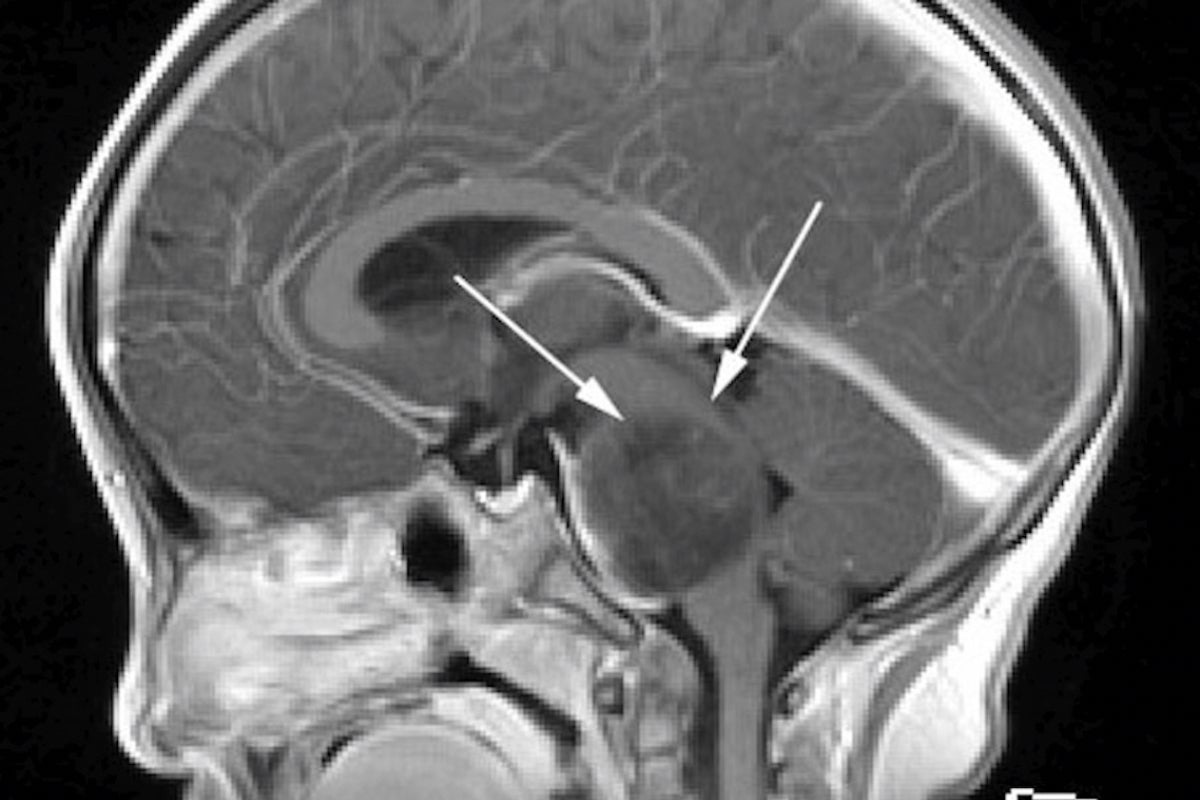

今回のフォーラムで取り上げる中心的な疾患は、DMGのカテゴリーの中でも、より難治性の高い「びまん性内在性橋グリオーマ」‥‥Diffuse Intrinsic Pontine Glioma(略称:DIPG)と称されるものです(図2)。これは、脳幹部の「橋」と言われる部位(図1)に悪性腫瘍が発生する病気で、年間約50名前後の子どもたちが発症します。生命活動にとって重要な神経が交差する場所に発生したがんは、中枢神経を毀損し、身体をまひさせ、その自由を奪っていきます。重要な神経が通る部位のため、そこにメスを入れての摘出手術は不可能であり、また、現時点では確定的な治療薬も見つかっていません。わずかに放射線治療により、一時的な寛解期が訪れますが、約半年以内で再発し、その後の治療法は無く、呼吸や血圧を維持できなくなり、やがてほぼ100%の確率で死に至ります。発症から1年以内に亡くなる確率は50%以上という、最も過酷な小児がんです。現在まで、世界中でこの病気の治療法が探索されて来ましたが、未だ形にはなっていません。しかし、近年、遺伝子解析技術の飛躍的発展によって、徐々に有効と思われる治療法が見つかりつつあります。

図1 脳の各部位

図2 DIPGのMRI画像